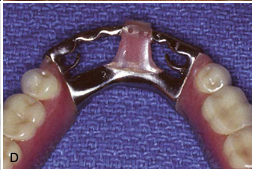

lingual bar major connector [illustration]

metal lingual bar major connector [illustration]